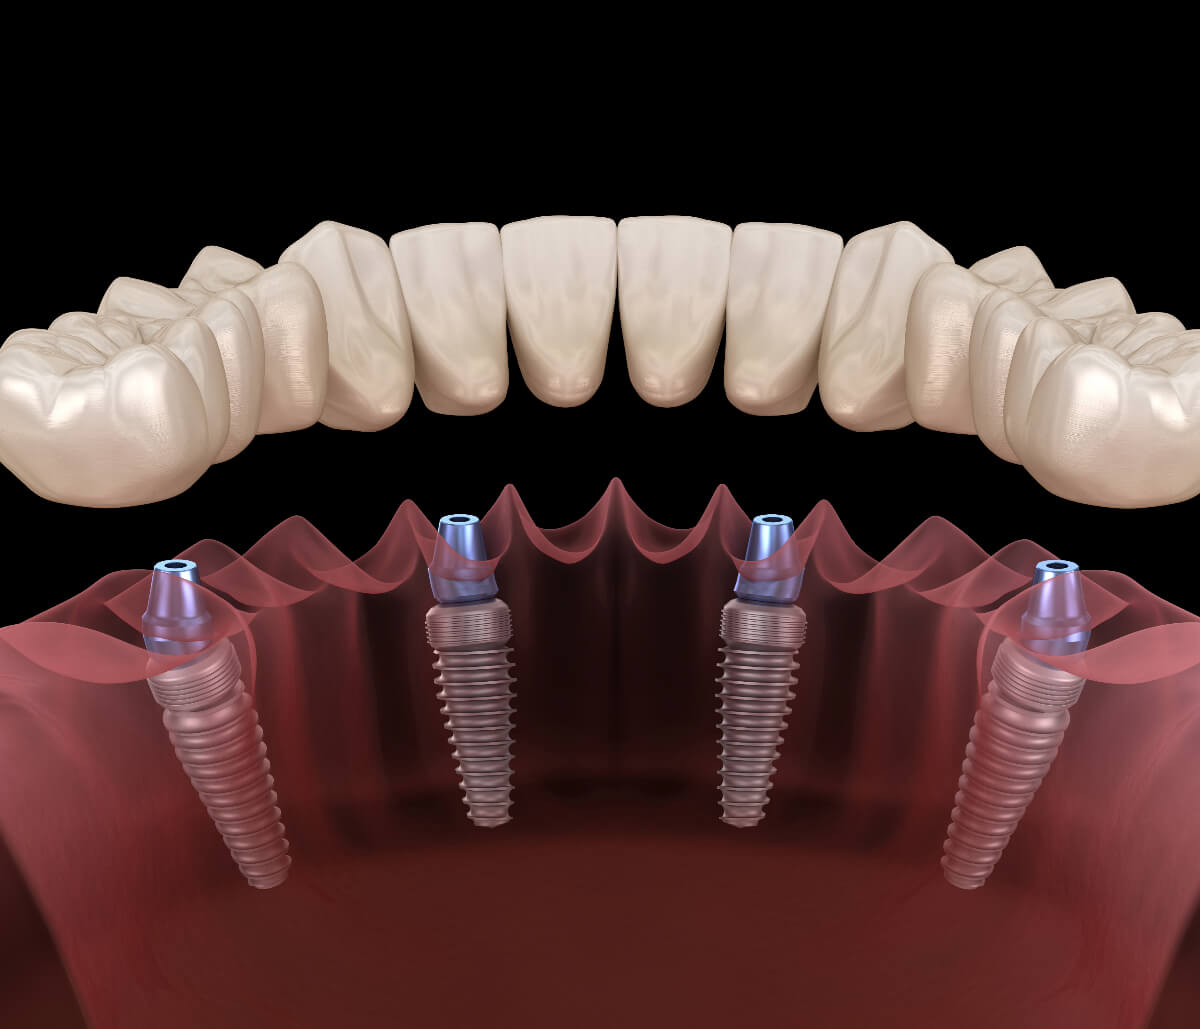

All-on-4 Dental Implants Prices: A Comprehensive Overview

While it’s unfortunate, complete tooth loss can happen to the best of us. Dental trauma, gum disease, and extensive tooth decay are some reasons you can lose most or all your teeth. Losing teeth — even one — can affect your oral function and self-confidence. Imagine losing all the teeth in an entire arch! It can be devastating. Peninsula Dental Implant Center understands what living without teeth feels like. We have invested in dental implantology to alleviate tooth loss frustrations and regain your winning smile. From single dental implants to All-on-4 dental implants and anything in between, we are your … Continue reading